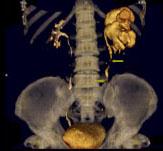

问题 男,58岁,尿频,尿痛伴低热乏力2月,CT如图所示,下列说法正确的是 ( )

选项 A、左侧输尿管结核 B、左侧输尿管癌 C、左侧输尿管多发性狭窄 D、左侧肾结核 E、左侧肾盂肾盏扩张,其边缘不整

答案 ACDE